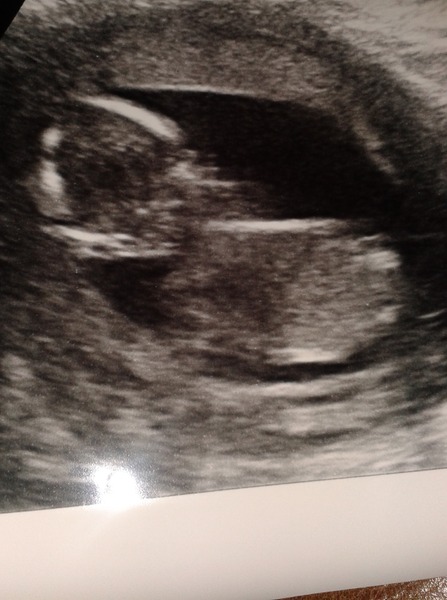

Never added a pic before so hope this works! This is my scan from today. She couldn't get a great pic because baby wouldn't move from one position so she told me to go and have a coffee. Wouldn't stop moving after that! She said couldn't give a definite for boy or girl though as still early days. Everything looks fine though. They were worried the tummy hadn't closed but it had.